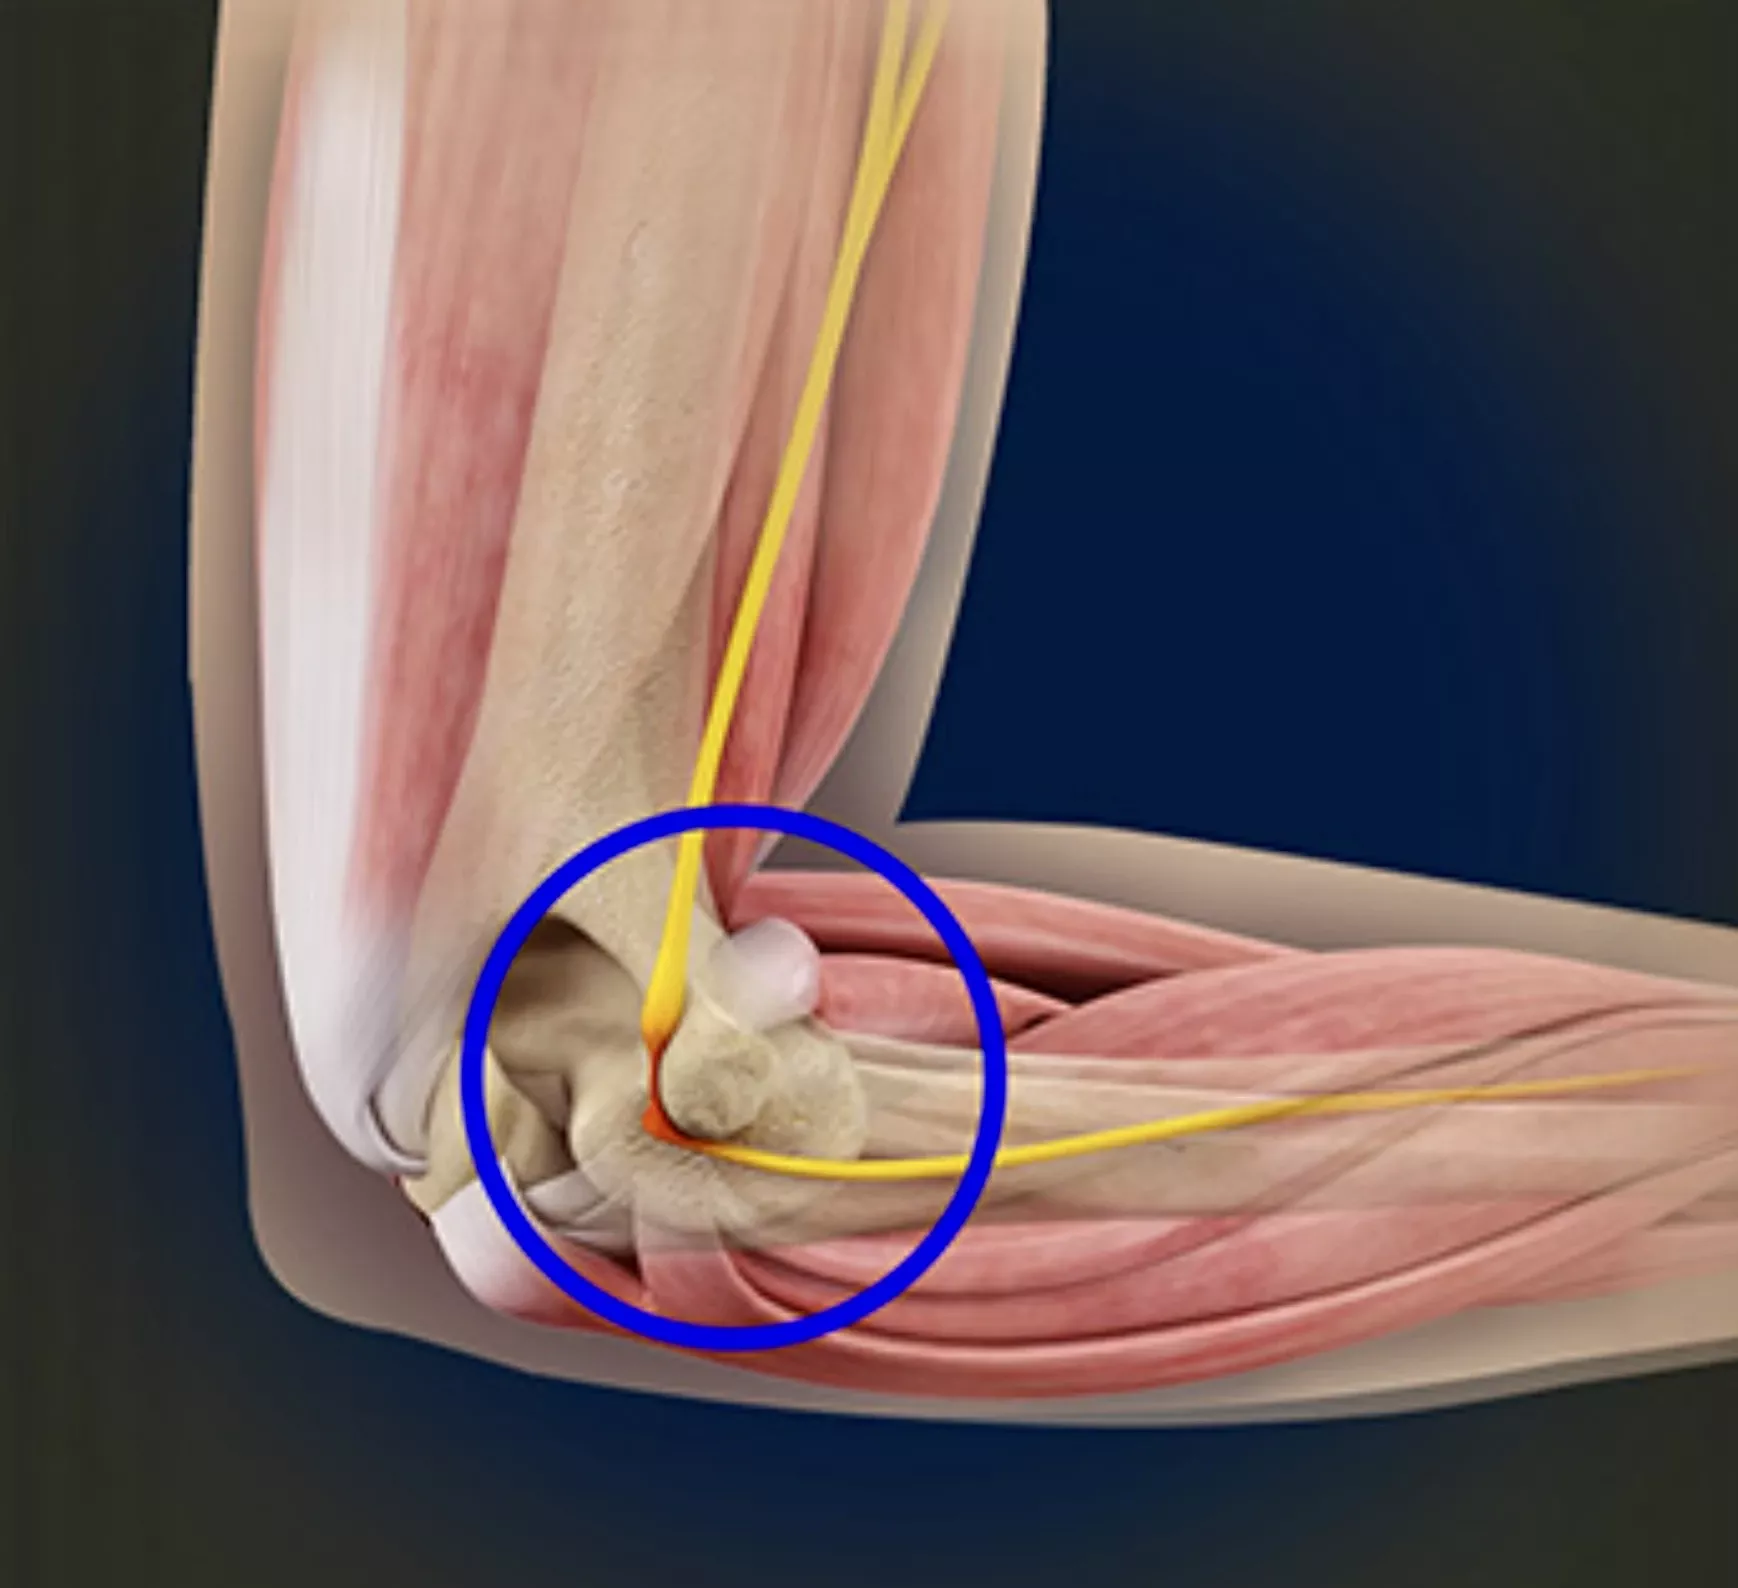

Cubital tunnel syndroom

Omschrijving

Bij dit syndroom komt er te veel druk op de nervus ulnaris aan de binnenzijde van de elleboog.

Klachten

- Tintelingen of doofheid in pink en ringvinger

- Verergering klachten bij leunen op de elleboog of langdurig plooien (telefoon, slapen)

- Soms krachtsverlies /onhandigheid in de hand

Behandeling

- Aanpassen van houding en activiteiten

- Nachtspalk om buigen van de elleboog te vermijden

- Bij ernstige of blijvende klachten: operatie om druk van de zenuw weg te nemen; soms wordt de zenuw verplaatst naar de voorzijde van de elleboog